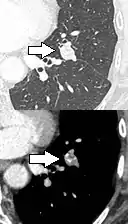

subpleural nodule.[9]

Round well-delineated solid lung nodule with smooth border.[9]

Lobulated nodule.[9]

Spiculated lung nodule.[9]

A "notch sign".[9]

A triangular perifissural node can be diagnosed as a benign lymph node.[9]